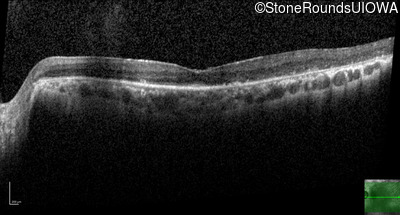

Age at visit: 71 years

Age at visit: 73 years

Age at visit: 75 years